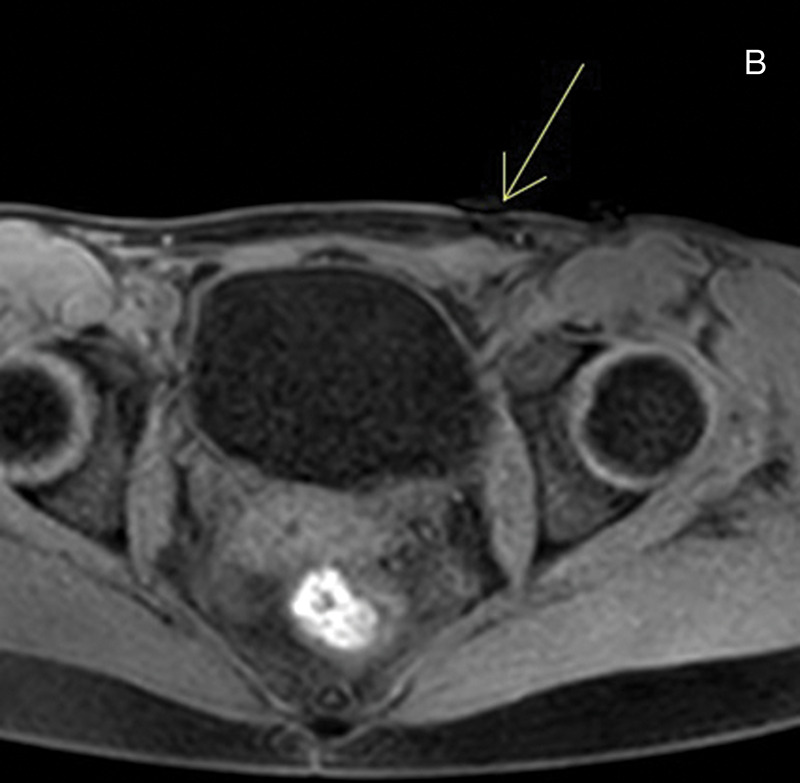

教学要点:磁共振成像(MRI)在诊断子宫内膜异位症中的作用越来越大,要求放射科医生熟悉深浸润性子宫内膜异位症的典型和非典型表现。

Teaching point: The role of magnetic resonance imaging (MRI) in diagnosing endometriosis is growing, requiring radiologists to become familiar with both typical and atypical presentations of deep infiltrating endometriosis.